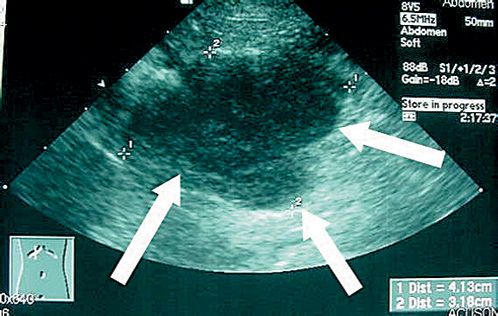

Please review the various causes of abdominal lymphadenopathy in cats.